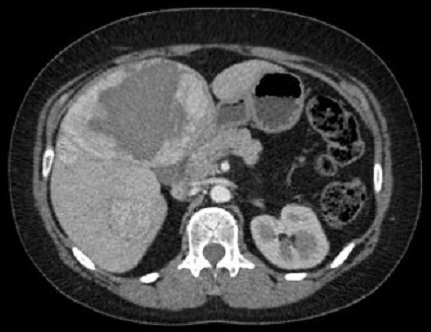

Image TDM de kyste du

foie : Image lesionaire arrondie , de taille variable souvent de

quelque centimetrique . Densite liquidienne de 0

a 15UH

Image radiologique TDM d'une kyste simple

du foie droit en coupe axiale : Aspect

lesionnel a densite variee de 7-15 UH ( hypodense )

avec bord lisse , bien definie et regulier |